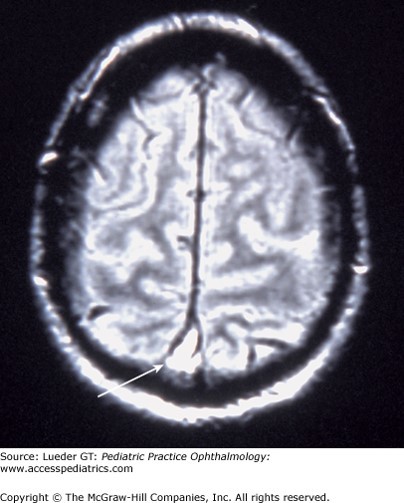

The correct answer is “C.” The early morning headache with nausea and papilledema on exam should clue you in to increased intracranial pressure as the underlying cause of the patient’s symptoms. Although option “D,” acute hydrocephalus, could also cause these symptoms, the patient would likely present in a more emergent manner with vomiting, altered level of consciousness, and possibly focal neurologic findings. Idiopathic intracranial hypertension (IIH), also known as pseudotumor cerebri syndrome, can be truly “idiopathic”; however, it is also associated with obesity, pregnancy, endocrinopathies, medications (tetracyclines, retinoic acid), vitamin A toxicity, and anemia. Although the neurologic exam in affected children should otherwise be normal, cranial nerve (CN) VI palsy is allowed as it is a “false localizing sign” of increased intracranial pressure.